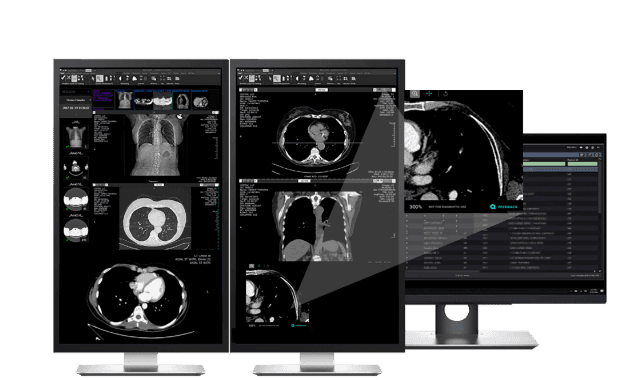

AI-анализ диагностических снимков

ИИ помогает интерпретировать диагностические снимки и дает врачу дополнительную опору при принятии клинического решения.